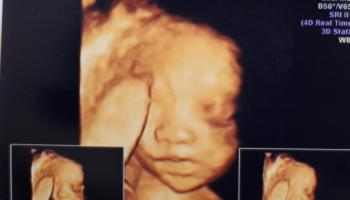

임신 22주 차 - 코가 날 닮아서 오똑~